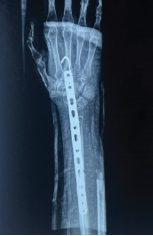

Clinical and Functional Outcomes of Proximal Humerus Internal Locking System Plate Fixation in Proximal Humerus Fractures: A Short-term Follow-up

Amit Saraf , Sandeep Bishnoi , Naman K Parakh , S Krishna Kumar , Ananya Chaudhary , K Dhanunjaya Reddy ………………………………p.329-333